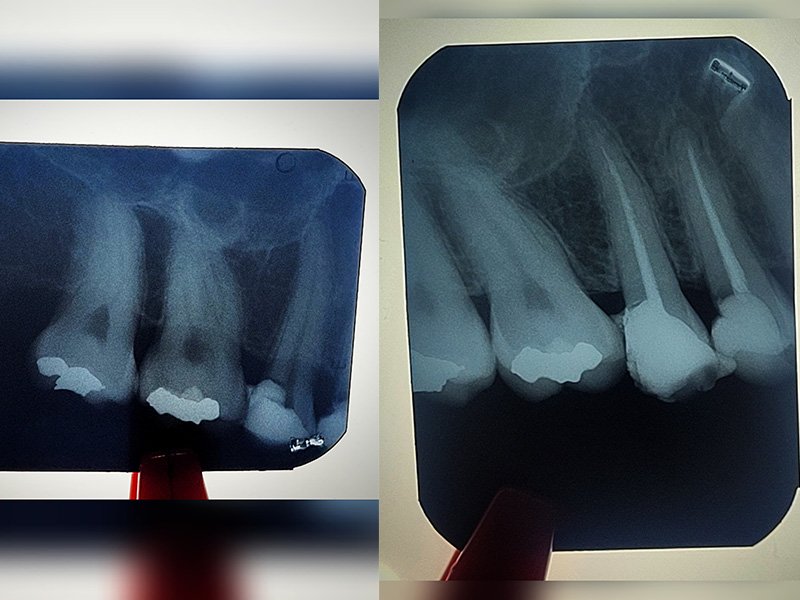

endodoncia

Endodoncia

- Endodoncia mecanizada.